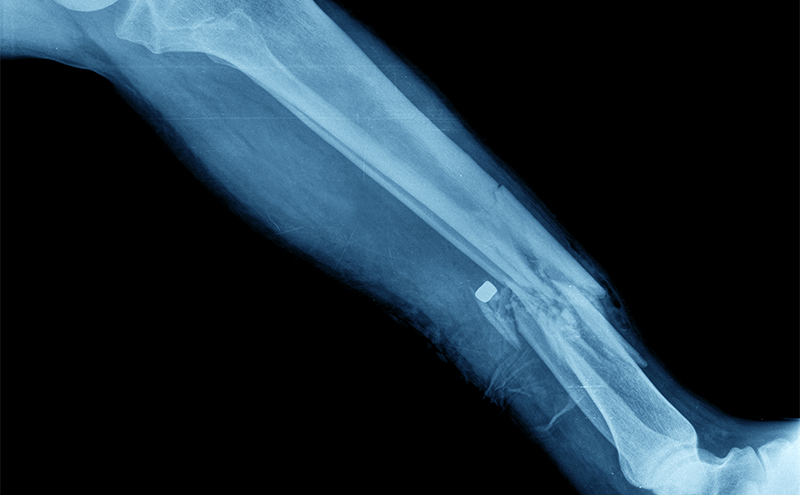

The patient had both lower extremities splinted in the emergency department by orthopedics and was given antibiotics and pain control. He was taken to surgery early the next morning for open reduction and internal fixation of the left trimalleolar fracture, intramedullary rodding of the right tibia, and irrigation and debridement of the open fracture. Following surgery, he was observed in PACU to have increased right leg pain, with firmness of the anterior and lateral compartments. Compartment pressure measurements were found to be greater than 50 mmHg. He was diagnosed with compartment syndrome and was taken back to the operating room for right lower extremity fasciotomy. Fasciotomy incisions were closed 3 days later. Following a 9-day inpatient stay, he was transferred to an inpatient rehabilitation facility for further physical and occupational therapy.

Right Tib-Fib Xray: Right angulated mid-shaft fracture of tibia and fibula